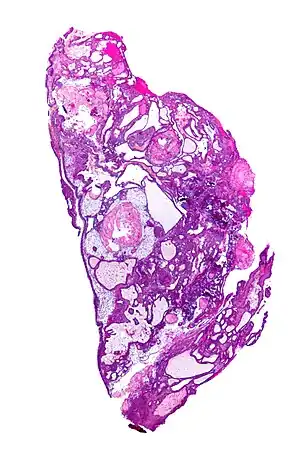

Very low magnification micrograph of an adamantinomatous craniopharyngioma. HPS stain.

On macroscopic examination, craniopharyngiomas are cystic or partially cystic with solid areas. On light microscopy, the cysts are seen to be lined by stratified squamous epithelium. Keratin pearls may also be seen. The cysts are usually filled with a yellow, viscous fluid rich in cholesterol crystals. Of a long list of possible symptoms, the most common presentations include headaches, growth failure, and bitemporal hemianopsia.